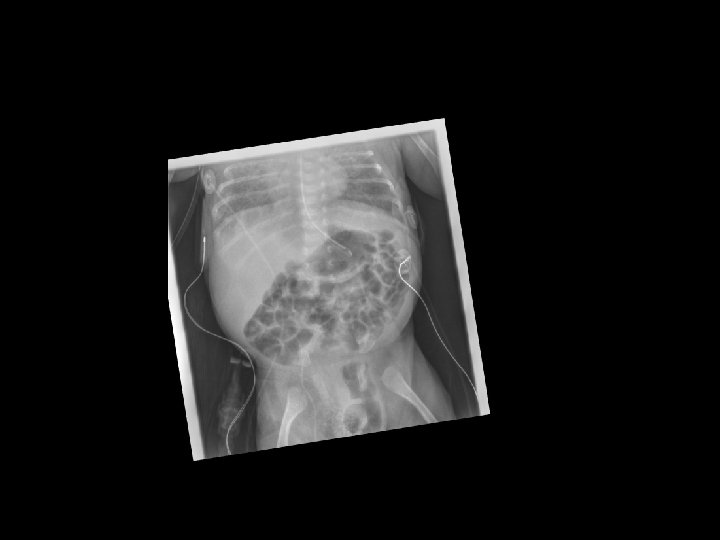

Case 1 Day 12 • On day 12 an Xray was done……

Case 1 Oh, oh…. . • On day 12…. – Free air noted on abdominal XR – No clinical abdominal symptoms • Rx…. – Intubated for transport – NPO – Antibiotic coverage expanded – Transported to Oakland Anna Bergquist CHO MR 960776